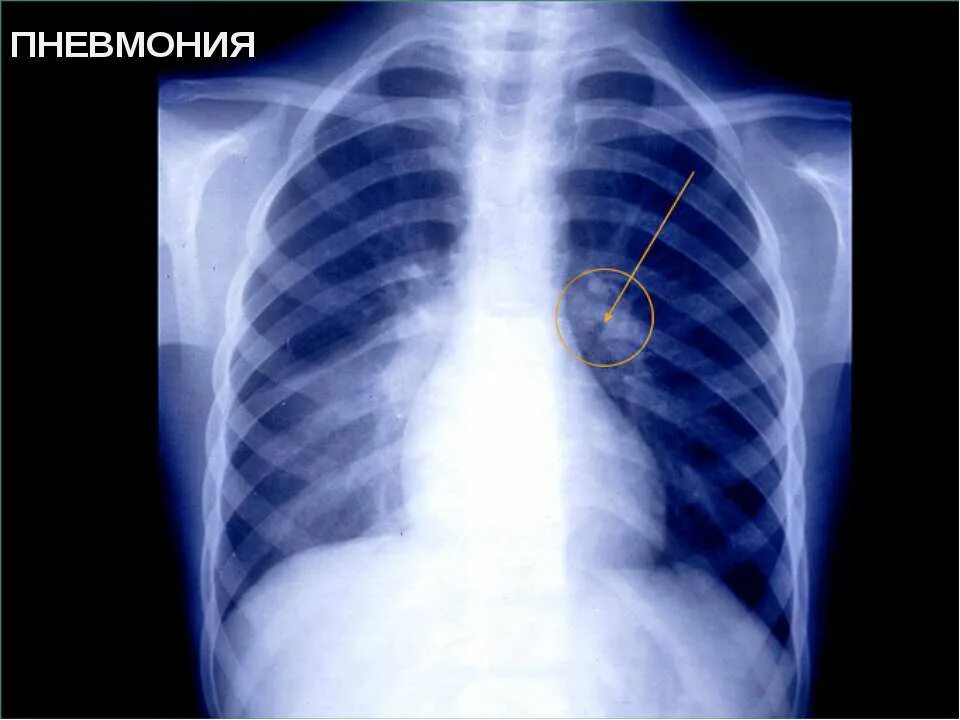

Как развивается воспаление легких